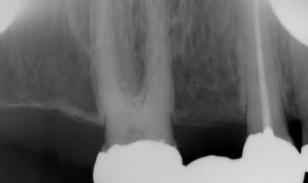

Apices Cut Off

What it looks like:

Roots of the teeth are missing from the image.

Cause:

Receptor not placed far enough into the mouth.

Fix:

Position receptor deeper.